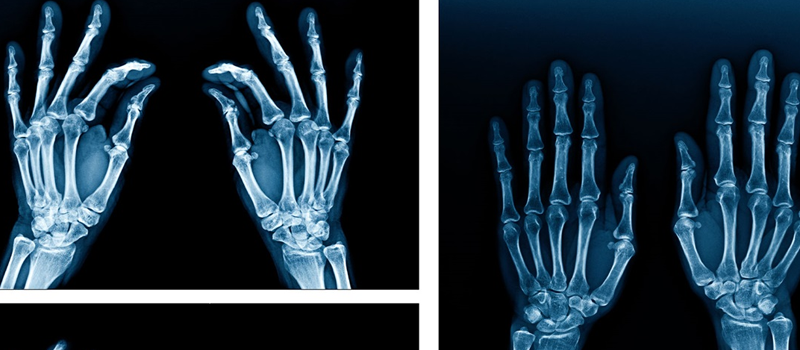

Arthritis. X-rays of your joints can reveal evidence of arthritis. X-rays taken over the years can help your doctor determine if your arthritis is worsening.